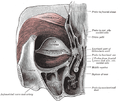

توعية الأنف

يغذي جوف الأنف ثلاثة شرايين:

- الشريان الوتدي الحنكي فرع الشريان الفكي العلوي.

- الشريان الغربالي الأمامي فرع الشريان العيني.

- الشريان الشفوي العلوي فرع الشريان الوجهي ويغذي دهليز الأنف.[1]